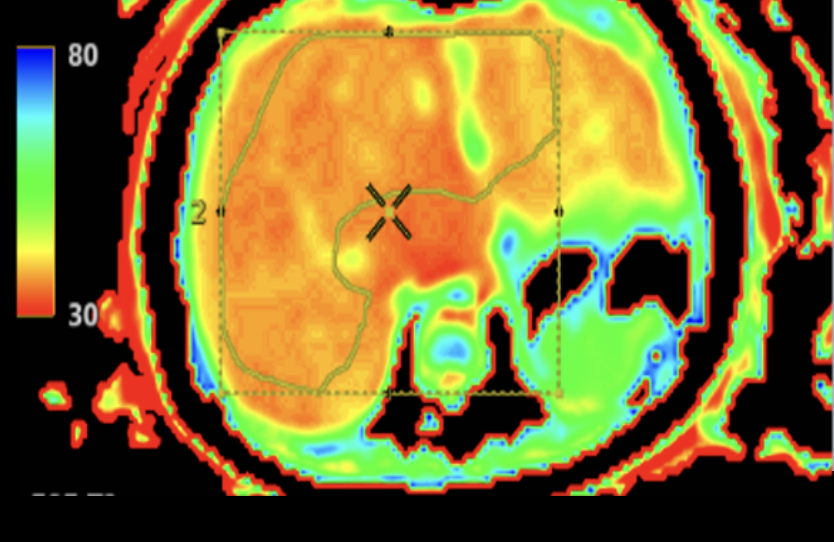

Det är en stor studie där barnen genomgår flera olika undersökningar under tre dagar. Det handlar bland annat om arbetsprov med gasanalys, hjärtultraljud, lungfunktionsundersökningar, MR av hjärta och lever, samt undersökningar av lymfsystem och blodkärl.

En annan viktig observation är att MR av hjärtat verkar ge den mest tillförlitliga bilden av hjärtfunktionen vid enkammarcirkulation. Forskarna har också sett att ökad stelhet i levern hänger ihop med förändringar i lungblodflödet.